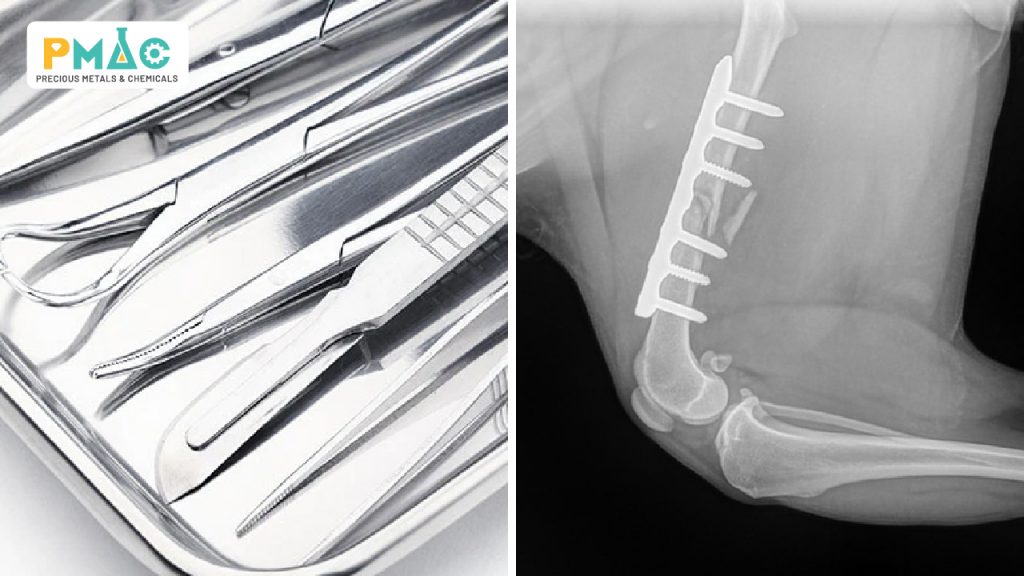

Hình 3: Ứng dụng của hóa chất xi mạ trong y tế

Trong ngành y tế, hóa chất xi mạ góp phần nâng cao hiệu năng và tuổi thọ cho các thiết bị y sinh:

– Xi mạ dụng cụ phẫu thuật như kìm, dao, bộ dụng cụ cắt ghép giúp tăng độ bền, chống oxy hóa và dễ khử trùng hơn so với bề mặt kim loại thô.

– Xi mạ trên các thiết bị cấy ghép — khi lớp phủ tương thích sinh học, các dụng cụ này đáp ứng các yêu cầu nghiêm ngặt về an toàn và giảm phản ứng mô khi đưa vào cơ thể.

– Lớp mạ kim loại như bạc có tính kháng khuẩn tự nhiên giúp hạn chế nguy cơ nhiễm trùng trong quá trình sử dụng y tế, đặc biệt trên bề mặt tiếp xúc trực tiếp với bệnh nhân.